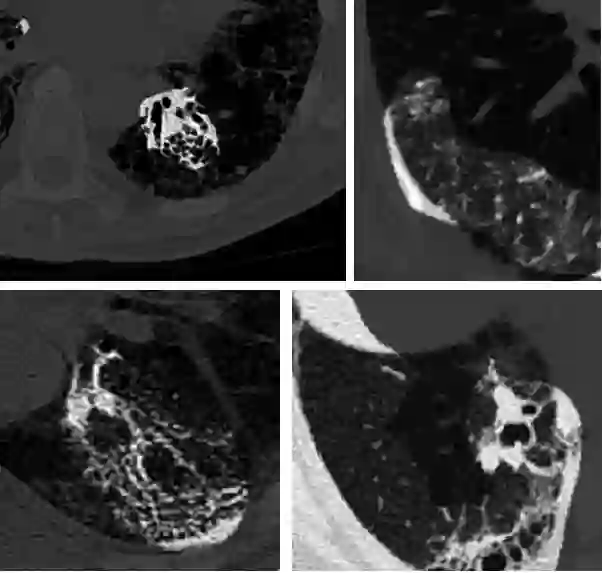

Pulmonary fibrosis is a devastating chronic lung disease that causes irreparable lung tissue scarring and damage, resulting in progressive loss in lung capacity and has no known cure. A critical step in the treatment and management of pulmonary fibrosis is the assessment of lung function decline, with computed tomography (CT) imaging being a particularly effective method for determining the extent of lung damage caused by pulmonary fibrosis. Motivated by this, we introduce Fibrosis-Net, a deep convolutional neural network design tailored for the prediction of pulmonary fibrosis progression from chest CT images. More specifically, machine-driven design exploration was leveraged to determine a strong architectural design for CT lung analysis, upon which we build a customized network design tailored for predicting forced vital capacity (FVC) based on a patient's CT scan, initial spirometry measurement, and clinical metadata. Finally, we leverage an explainability-driven performance validation strategy to study the decision-making behaviour of Fibrosis-Net as to verify that predictions are based on relevant visual indicators in CT images. Experiments using a patient cohort from the OSIC Pulmonary Fibrosis Progression Challenge showed that the proposed Fibrosis-Net is able to achieve a significantly higher modified Laplace Log Likelihood score than the winning solutions on the challenge. Furthermore, explainability-driven performance validation demonstrated that the proposed Fibrosis-Net exhibits correct decision-making behaviour by leveraging clinically-relevant visual indicators in CT images when making predictions on pulmonary fibrosis progress. While Fibrosis-Net is not yet a production-ready clinical assessment solution, we hope that its release in open source manner will encourage researchers, clinicians, and citizen data scientists alike to leverage and build upon it.